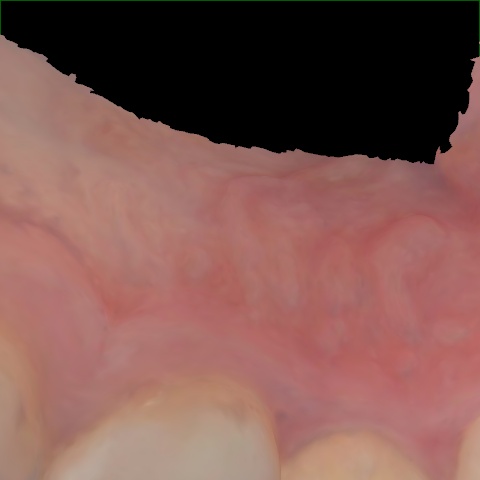

Annotated as "Good"